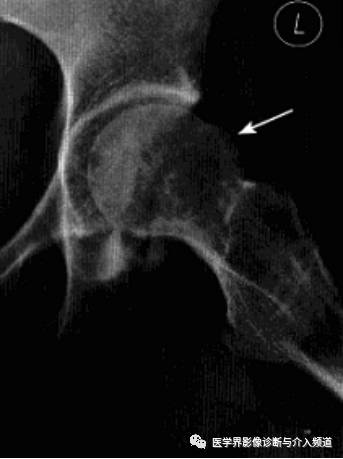

影像诊断:X线平片是基本检查方法,直立骨盆正位及髋关节侧位片。

平片:①凸轮撞击型,正位片示头颈连接处扁平,呈“左轮枪柄”样畸形,侧位片示股骨头颈凹陷减少,中心边缘角变小<16度,②钳夹撞击型,髋臼窝过深,髋臼后倾,呈相交8字征,偏心距缩短<9mm。

CT:三维CT可测量股骨头颈连接处前外侧偏移量减低,股骨头颈联合处前上缘可见骨性突起。